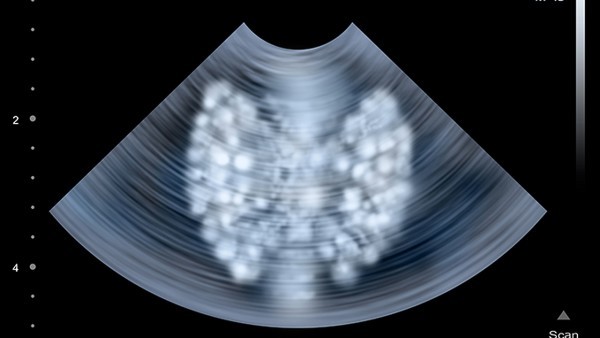

孕妇产检做B超对胎儿影响

正常状况下孕妇产检做B超是不会对胎儿造成什么伤害的,由于B超大夫都是经由专业严厉的训练哦,大夫会把B超的调理到一个正常领域内,以是这个孕妇产检做B超是不会有什么影响的,而孕期做B超也是保障胎儿正常发育的一项重要手腕之一哦,需求唤醒的是孕妇每次做B超的时间不宜超越五分钟哦。孕妇产检做B超注意事变